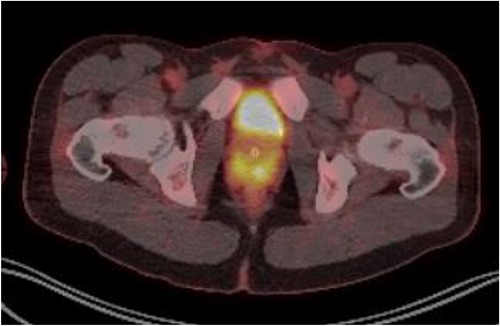

Laboratory tests of full blood count and liver function test were unremarkable with prostate specific antigen of 0.53. Mid-stream urine MCS did not show any infection and urine cytology was negative. Renal function test revealed progressive worsening of previously normal eGFR down to 27 ml/min. Initial renal tract ultrasound (Fig. 1) showed enlarged prostate indenting into the bladder base with high post micturition urine residual volume of 185 ml but no hydronephrosis. CT KUB (Fig. 2) showed irregularly enlarged prostate with bilateral hydroureteronephrosis. MRI prostate showed enlarged prostate with PIRADS 5 amorphous mass suspicious for carcinoma involving bilateral seminal vesicles and right vesicouretric bladder. FDG PET (Fig. 3) showed unusual distribution pattern of lymphoma involving the prostate with bilateral symmetrical renal, early pulmonary, and possibly right thyroid lobe involvement.

PET FDG scan pre-R-CHOP chemotherapy showing disease activity in the prostate.